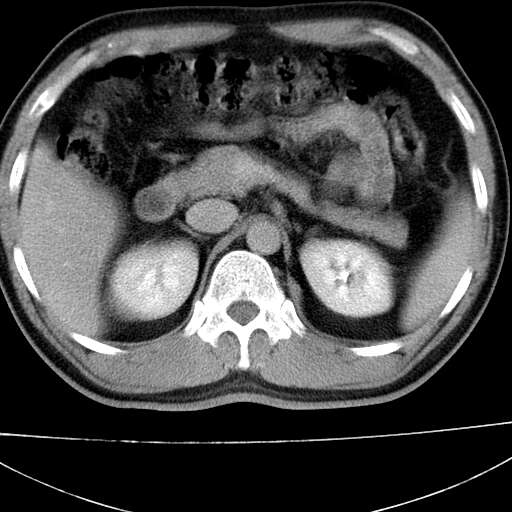

标题: CT21921:腹膜后腔肿物。患者男39Y。体检。增强扫描时间欠准

1)考虑左肺下叶后基底段(或左下胸后壁胸膜)软组织团块,性质待定;建议行进一步检查。2)左肾结石。

左膈肌角后腹膜腔见肿物影,其内见脂肪密度灶及软组织密度灶,强化不明显。病灶大部在后腹膜内。考虑异位嗜铬细胞瘤或脂肪肉瘤、畸胎瘤

1)考虑左肺下叶后基底段软组织团块,性质待定;建议行进一步检查。2)左肾结石。

左膈肌连续性中断,左侧膈疝可能性大

左下肺隔离症,可见从胸主动脉发出异常血管供应